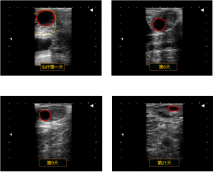

吉彩网一般来说,通过直肠检查进行的牛生殖诊断和妊娠诊断可能会误诊,准确的判断需要技巧。 牛用B超是一种针对母牛妊娠检测的一种方法,由于可以实时观察动态图像,因此可靠性高。……

吉彩网母猪的背膘厚度检测主要通过猪用B超机检测母猪P2位置进行,高背膘后备母猪比低背膘后备母猪更早进入青春期。……

使用兽用B超机对马做超声检查提供了比直肠触诊更早地诊断怀孕、有效管理双胞胎和检测即将发生的早期胚胎死亡的机会。……

吉彩网廉价、轻便、便携式猪用B超机的出现将极大地促进母猪的生殖成像,并可能有助于做出管理决策,这可以基于对后备母猪或母猪在任何时候的生殖状态的准确诊断。……

羊用B超对母羊妊娠扫描已成为管理母羊群繁殖性能的重要工具。使养殖者能够做出正确的管理决策,从而提高羊场生产力和盈利能力。……